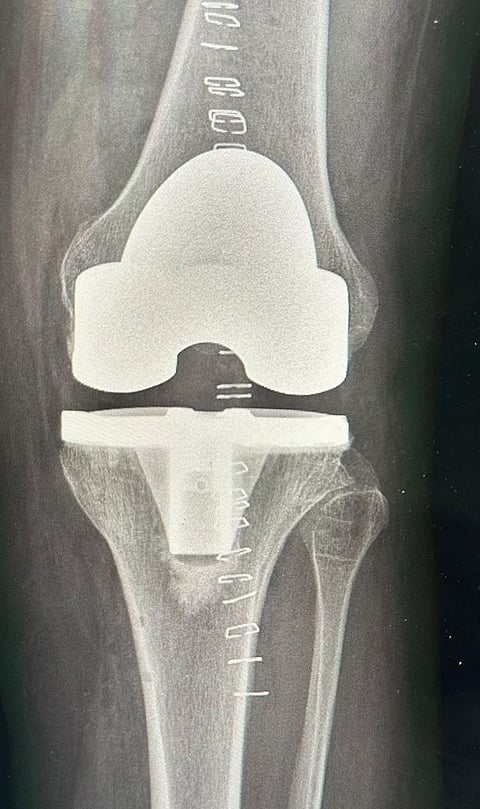

وبعد التقييم الدقيق، أُجريت العملية باستخدام الروبوت الجراحي لإزالة الاحتكاك وتعديل الانحراف وتركيب المفصل بالتقنية الحديثة، مما أسهم في تخفيف الألم واستعادة القدرة على الحركة وثني الركبة بشكل طبيعي.